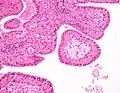

The appearance of this tumor under the microscope is unique. There are cystic spaces surrounded by two uniform rows of oncocytes, which are epithelial cells with abundant, granular, eosinophilic cytoplasm.[7] The cystic spaces have epithelium referred to as papillary infoldings that protrude into them. Additionally, the epithelium has lymphoid stroma with germinal center formation.

Histopathology of Warthin tumor in the parotid gland. Another view of a file "Warthin tumor (1).jpg". H&E stain. -

Histopathology of Warthin tumor in the parotid gland. Higher magnification of a file "Warthin tumor (1).jpg". H&E stain. -

Intermediate magnification micrograph of a Warthin tumor. -